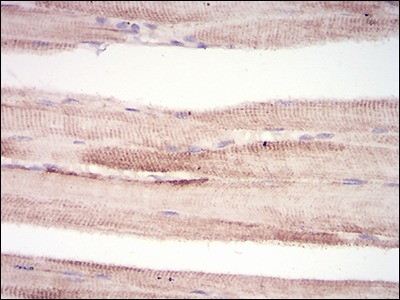

| Verified Activity | 1. Immunohistochemical analysis of paraffin-embedded human rectum cancer tissues using anti-MuRF1 antibody. Counter stained with hematoxylin. 2. Immunohistochemical analysis of paraffin-embedded huamn muscle tissues using anti-MuRF1 antibody. Counter stained with hematoxylin. 3. ICC staining MuRF1(green) and Actin filaments (red) in Hela cells. The nuclear counter stain is DAPI (blue). Cells were fixed in paraformaldehyde, permeabilised with 0.25% Triton X100/PBS. 4. Flow cytometric analysis of Hela cells with MuRF1 antibody at 1/100 dilution (green) compared with an unlabelled control (cells without incubation with primary antibody; red). ![]() ![]() ![]() ![]() |